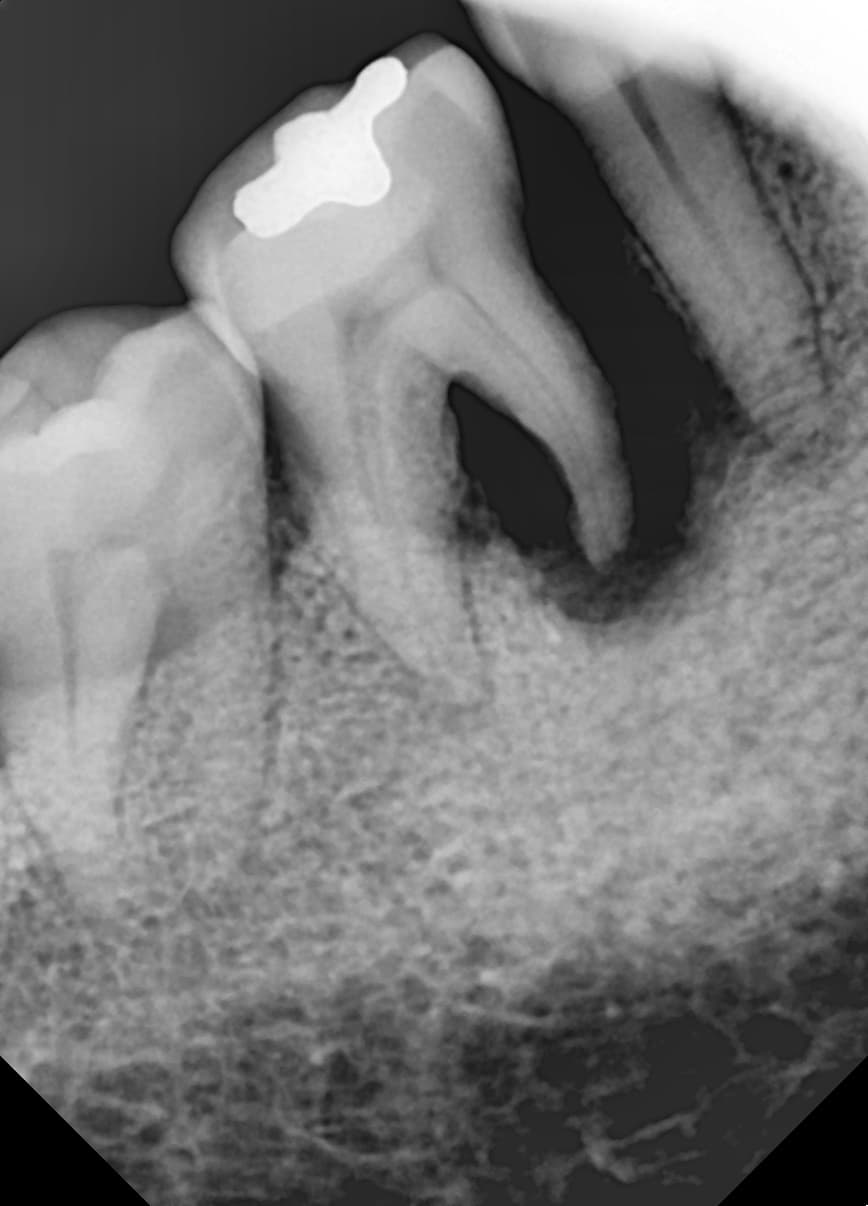

"Suyak juda ko'p yemirilgan edi,

milk davolash orqali suyak tiklanib ketdi"

Og'ir milk kasalligi tufayli suyak ko'p yemirilgan holat

Milk davolash va suyak ko'chirish orqali suyak tiklanib, implant muvaffaqiyatli o'rnatildi